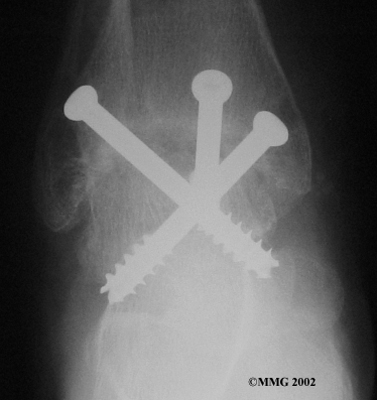

Ankle Fusion

When the ankle joint becomes so painful that it is difficult to walk, surgery may be suggested to fuse the ankle joint. An ankle fusion is sometimes also called an ankle arthrodesis. In this operation, the three bones that make up the ankle joint (the talus, the tibia, and the fibula) are allowed to grow together, or fuse, into one bone. Once this is done the ankle no longer is able to move, but with a successful fusion the pain is gone. Most people with a successful fusion of the ankle are able to walk without much trouble, and in some cases it is almost impossible to tell that the ankle is stiff. But it is very difficult to run because you lose the ability to push off with the toes. The foot can't bend down.

Most people will need some changes made to their shoes following an ankle fusion. Because the ankle no longer moves, it is difficult to roll over the top of the foot when you take a step. For this reason, shoes are usually fitted with a rocker sole. This allows the shoe to roll instead of the foot. A special heel is sometimes built on the shoe to absorb some of the shock.

The ankle fusion is a good operation, especially for a young, active person. It is usually the preferred option for post-traumatic arthritis of the ankle. Once the ankle is successfully fused it can last a lifetime, and no other operations are expected later unless there are problems. But there are complications associated with the ankle fusion, and not all ankle fusions are successful.